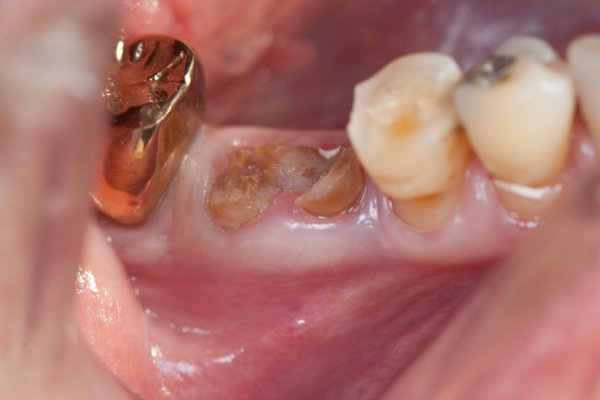

Ganz besonders kommt es bei Zahnimplantationen gleich nach der Extraktion an, dass der Patient das an der Wunde entstandene Blutkoagel nicht wegspült oder wegputzt. Dies wird verhindert durch Einbringen einer Heilkappe die zum Zahnimplantatsystem gehört und auf den Zahnfleischformer des Zahnimplantates aufschnappt sowie einer Fixationsnaht. Ist der Patient innerhalb der ersten 3 Tage sehr vorsichtig, und befolgt Anweisungen von Zahnarzt München kommt es regelmäßig zu so schönen umkomplizierten Erfolgen. Das minimalinvasive Zahnimplantat heilt viel schneller ein, da die versorgenden Blutbahnen nicht abgeschnitten werden. Das eigene stabile Blutkoagel hier stabilisiert durch Gelatine und Lokalantibiotikum Leukase heilt viel schneller als synthetischer Rinderknochen der früher oft verwendet wurde. Dieser muss sich nach der Zahnimplantation erst abbauen und kann erst dann in eigenen Knochen umgewandelt werden. In körperfremden Rinderknochen der isoliert im eigenen Knochen liegt, lässt sich nämlich kein Zahnimplantat sicher implantieren. In diesem Fall konnte dem Patienten ein mühevoller langwieriger Knochenaufbau erspart werden. Das Gute daran, man kann nur gewinnen, nicht verlieren denn - im schlimmsten Fall hätte bei Nichteinwachsen das Implantat wieder entfernt werden müssen. Einen Knochenaufbau kann man dann immer noch erstellen. Zu Misserfolgen kommt es viel öfter bei klassischem Knochenaufbau. Viel hängt von der Heiltendenz des Patienten ab. Der Patient gibt uns oft schon vor der OP einen Hinweis, viele behaupten gutes oder schlechtes Heilfleisch zu haben. Rauchen verdoppelt die Einheilzeit, womit sich leider auch die Wahrscheinlichkeit des Implantatverlustes innerhalb eines Jahres von 5 von 1000 Fällen (bei Nichtrauchern) auf ca. 50 von 1000 Fällen erhöht. Schon nach nur 6 Wochen kann der Abdruck für die Zirkonkronen genommen werden. Nach Abnahme der Heilkappe ist ein wohlgeformtes Zahnfleisch zu erwarten.